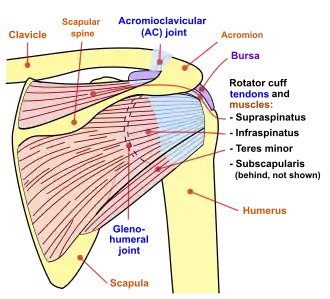

The intrinsic muscles of the scapula include the muscles of the rotator cuff(SITS muscle)—the subscapularis, supraspinatus, infraspinatus and teres minor.[3] These muscles attach to the surface of the scapula and are responsible for the internal and external rotation of the shoulder joint, along with humeral abduction.

The extrinsic muscles include the biceps, triceps, and deltoid muscles and attach to the coracoid process and supraglenoid tubercle of the scapula, infraglenoid tubercle of the scapula, and spine of the scapula. These muscles are responsible for several actions of the glenohumeral joint.

Diagram of the human shoulder joint, back view

Diagram of the human shoulder joint, back view -